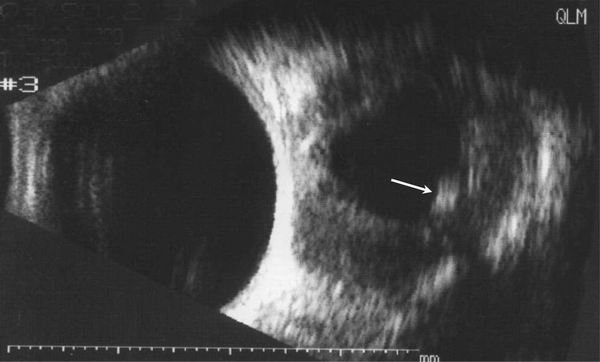

患者男性10岁。籍贯河南。 左眼球渐进性突出,间断红肿2年。曾用抗生素+激素治疗有效。但反复发作,眼球突出加重。于2000年5月住院治疗。入院检查:全身正常。眼科检查:双眼视力1.0。左眼眼睑无红肿,眼球突出测量:右眼12㎜,左眼18㎜,眶距95㎜。眶压增高,眼球突出,轻度外移位,内收明显受限,外展仅30°(图1)。眼底后极部轻度水肿。CT扫描如图2。入院期间左眼突然红肿,眼球突出加重,眶压增高,轻度恶心(图3)。